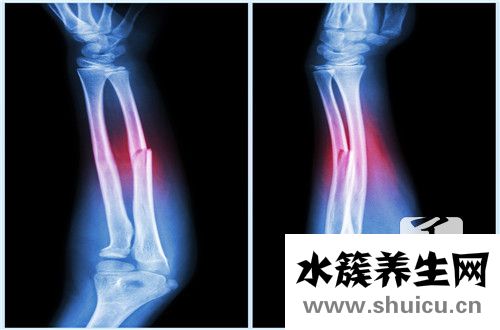

3、跌打損傷淤腫病人不適合服用。花生仁頗具一種因素,稱為促凝血因子。說白了便是跌打的病人他假如服用了花生仁,那麼他本身的傷處便會造成血瘀不可以消退起來,會加劇病況,非常容易引起腫疼,沒法盡快地恢復癥狀。

骨折與其他疾病的區別在于,患者需要更長的療養時間,尤其是對于某些中老年人。 骨折后,無法治愈。 所有人都說,如果您在100天內進行了大量更改,better骨頭骨折會改善多長時間? 如果是較為輕度骨折,則可以...